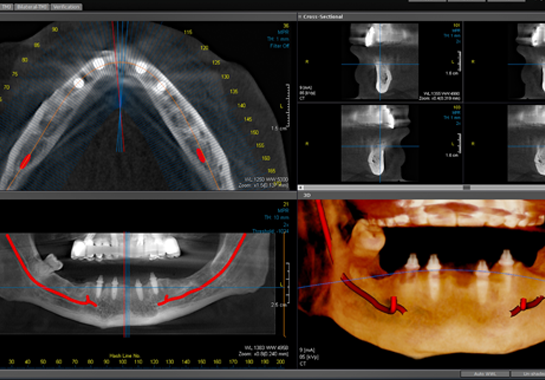

La consultation de planification

Tout commence par une consultation approfondie et une planification détaillée. Le chirurgien-dentiste réalise un examen clinique minutieux, complété par des examens radiologiques avancés comme la tomodensitométrie 3D. Ces informations permettent de choisir le type de greffe le plus approprié et de planifier précisément l’intervention.

L’intervention elle-même débute par une incision précise de la gencive pour accéder à l’os sous-jacent. Le site receveur est soigneusement préparé pour accueillir le matériau de greffe. Celui-ci est alors mis en place avec précision, parfois accompagné de membranes de régénération pour guider la croissance osseuse. L’intervention se termine par la suture méticuleuse de la gencive.